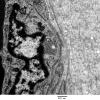

PERIPHERAL NEUROPATHY

11 VASCULITIS - VASCULOPATHY

2 Vasculopathy (2)